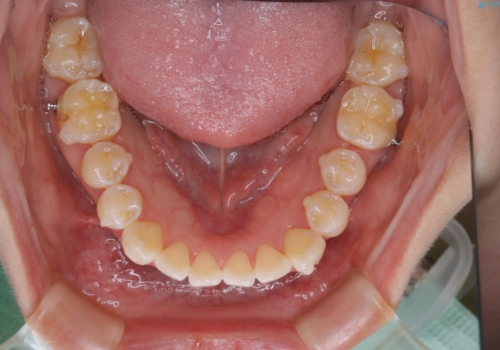

前歯で噛めない:オープンバイト(開咬)を非抜歯インビザラインで治療

- 上下の歯が噛んでいないことを気にしてご相談にいらした方です。

舌癖も認められたため、舌のトレーニングも併せて行い、矯正治療の効率化を図ると同時に後戻りのリスクを最小限に抑えるようにしました。

オープンバイトの方への治療は、通常抜歯を行いワイヤーによる矯正治療を行うことが多いですが、今回はインビザラインの特性を生かし、非抜歯にて綺麗な歯並びを作ることが出来ました。

舌癖がある方は、歯を内側から押し出す力が日常的に働くため、矯正治療後も歯と歯の隙間が開いてしまうなどの後戻りのリスクが高いことが知られています。舌の正しいポジショニングやお口周りの筋肉のトレーニングを行うことで後戻りのリスクを減らすことが可能です。